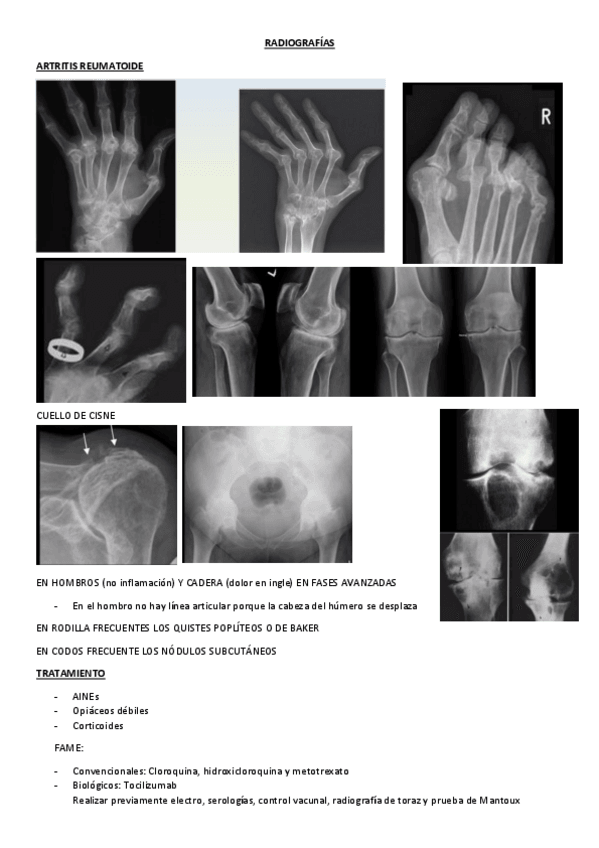

He publicado nuevos apuntes de 2º Cuidados de Enfermería en Procesos Osteoarticulares: RXs-REUMA-POWERS.pdf

7 páginas